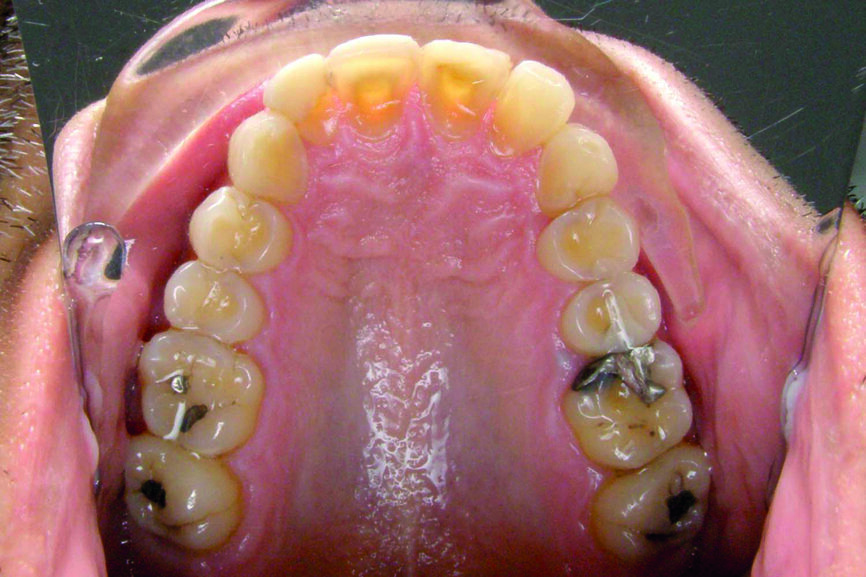

– La radio panoramique8

met en évidence la présence de deux dents de sagesse incluses (18 et 28), l’agénésie des 38 et 48 et la présence d’un odontome au niveau de la 24. On devine par ailleurs sur le cliché les overlays des dents 34, 35, 37, 44–47. La dent 46 présente un traitement endodontique très satisfaisant, et une coiffe prothétique parfaitement adaptée. On devine l’abrasion importante des incisives mandibulaires qui a motivé la première consultation de notre patient l’année précédente.